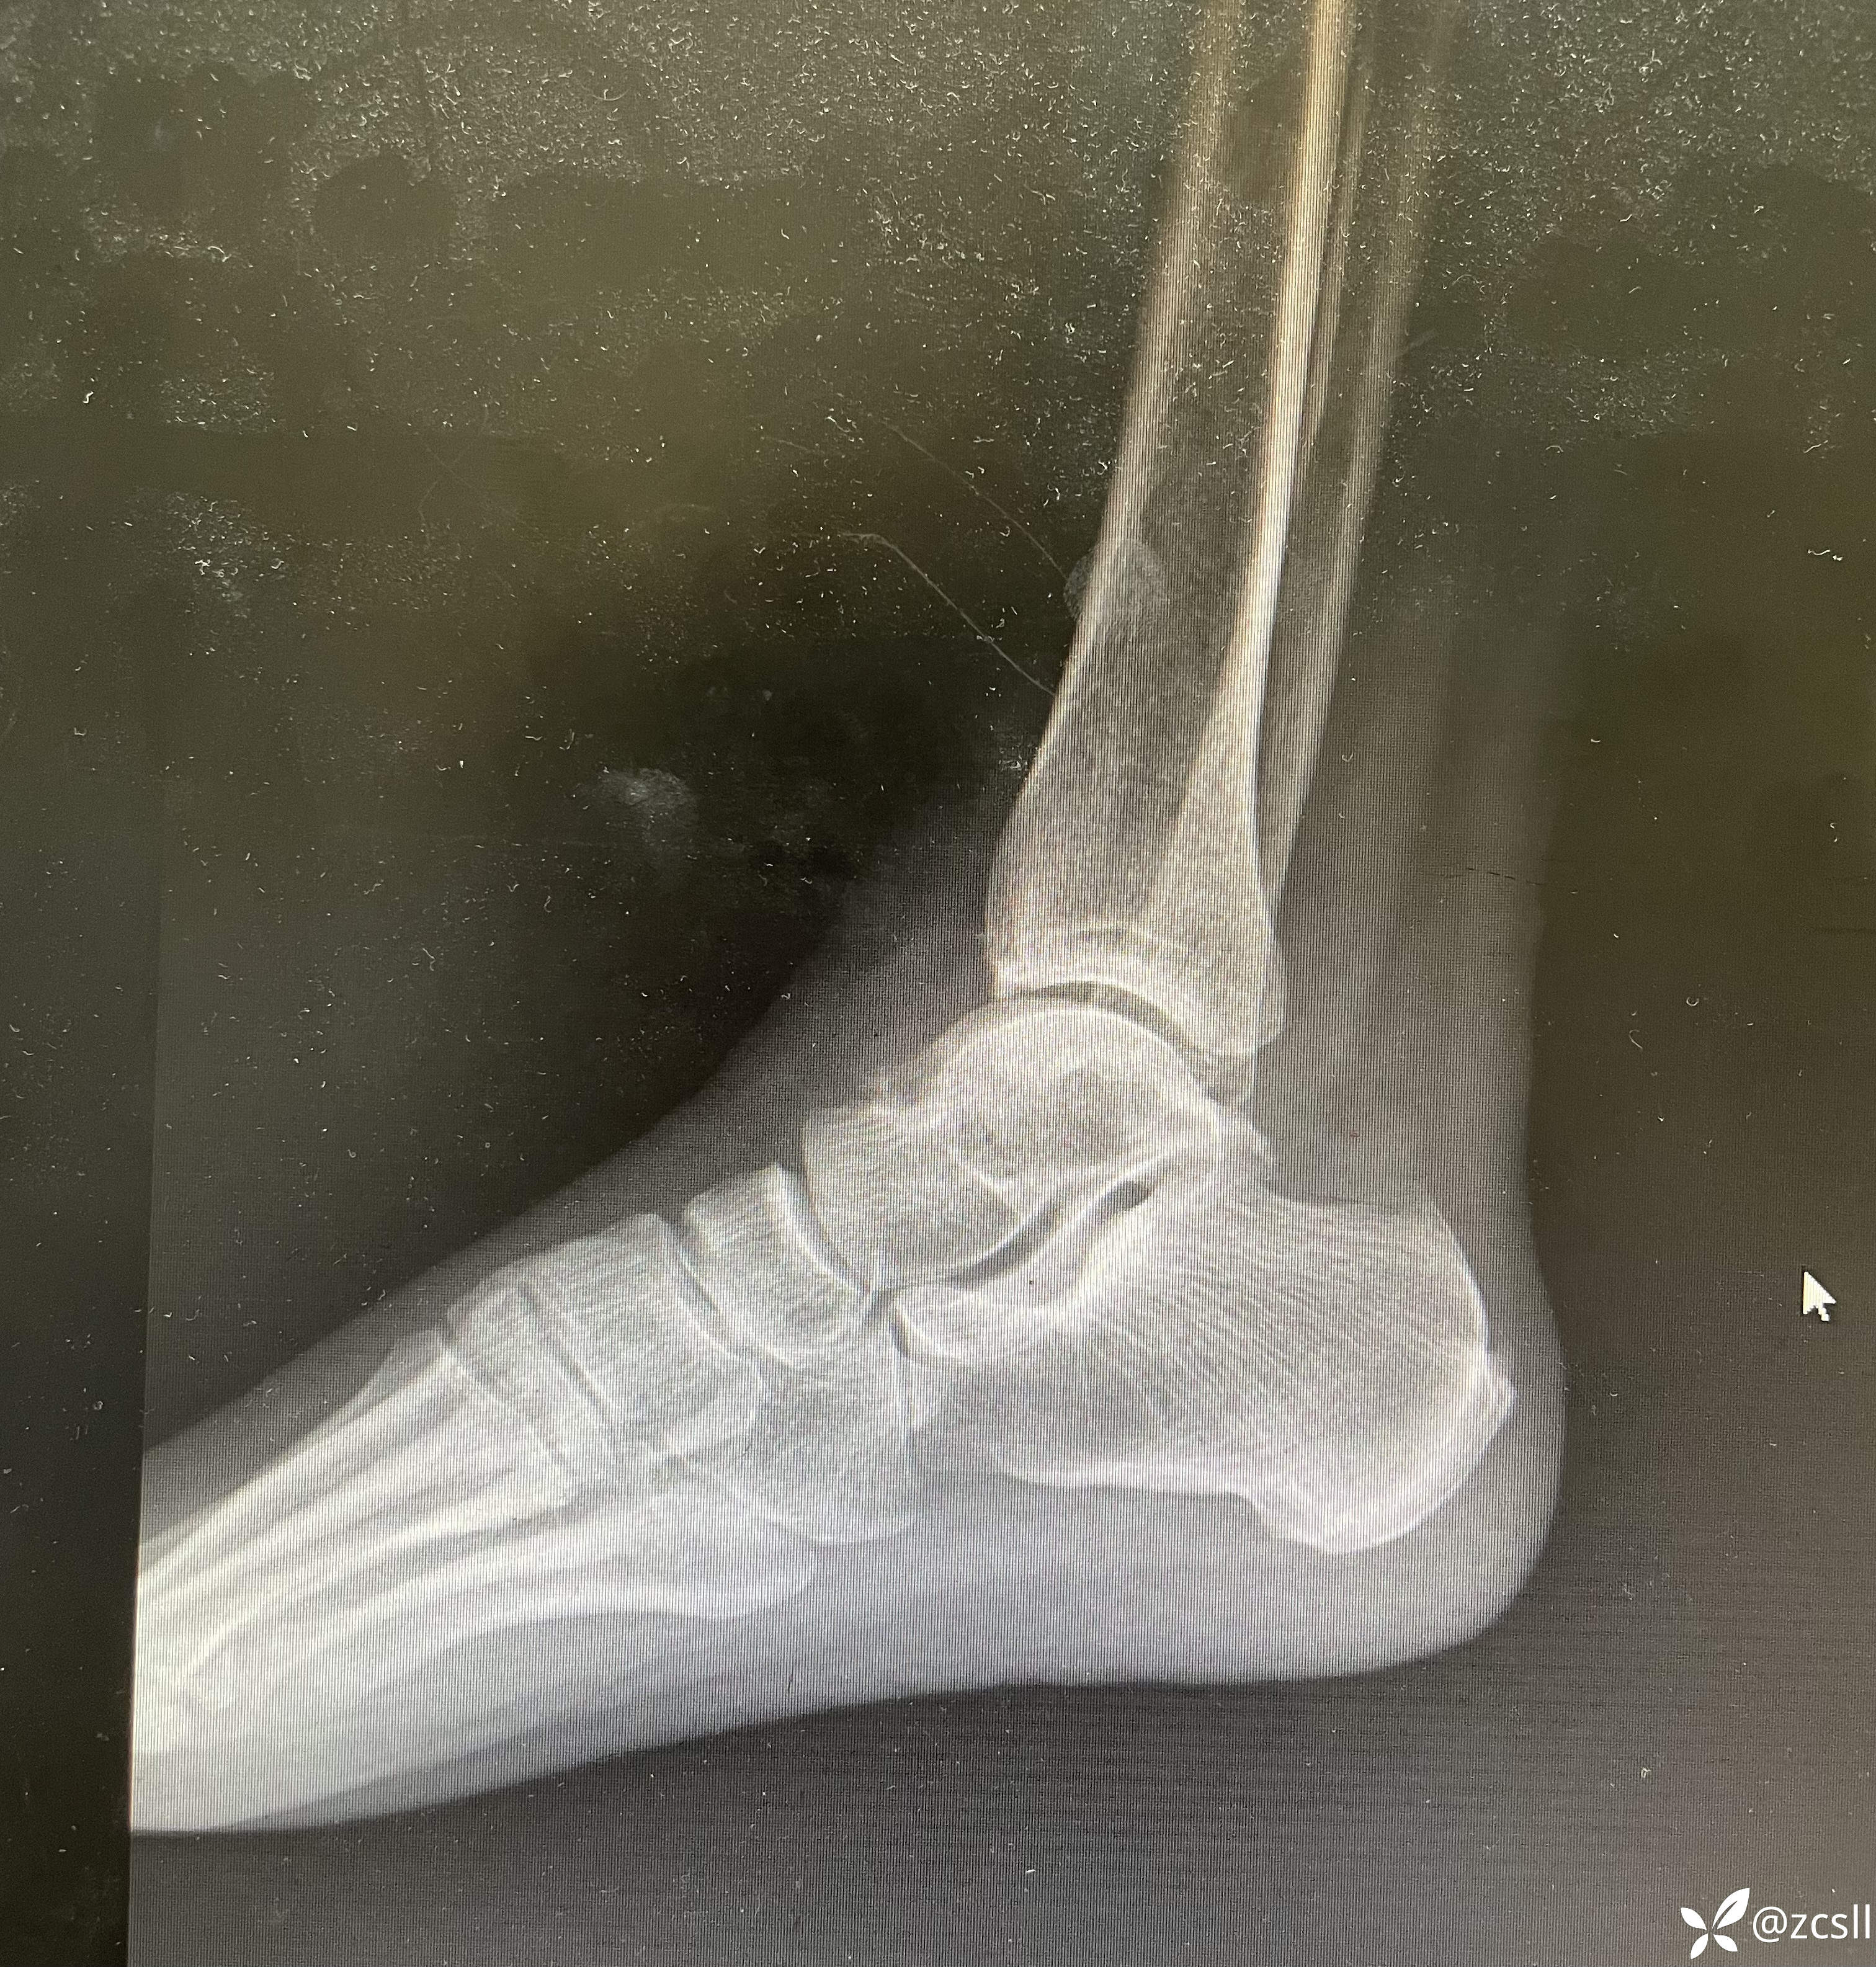

女性,59岁,双踝关节疼痛,局部无红肿,关节彩超提示双轨征,晶体性关节炎不排除。完善踝关节x片提示痛风石?该患者无高尿酸血症病史,入院查血尿酸410。针对这个患者,到底是真痛风还是假痛风呢?期待,路过的同仁能帮助分析分析。